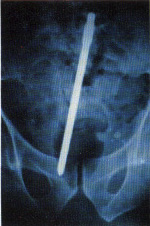

Fig. 52.7

(c) A

live shell, which needed careful handling.